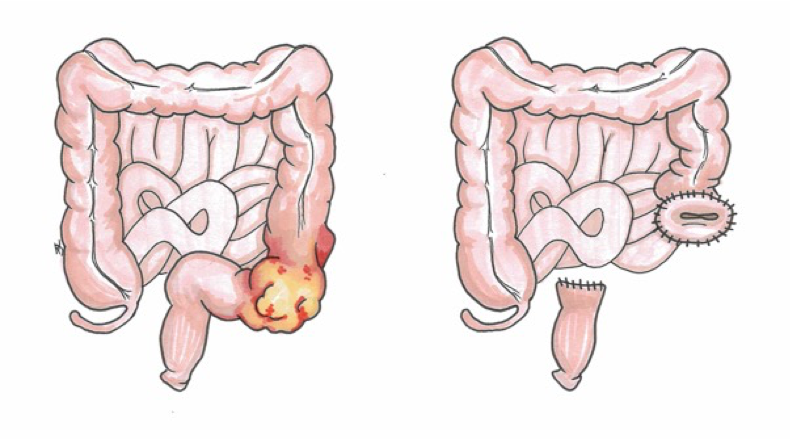

Sigmoid colon tumour obstruction